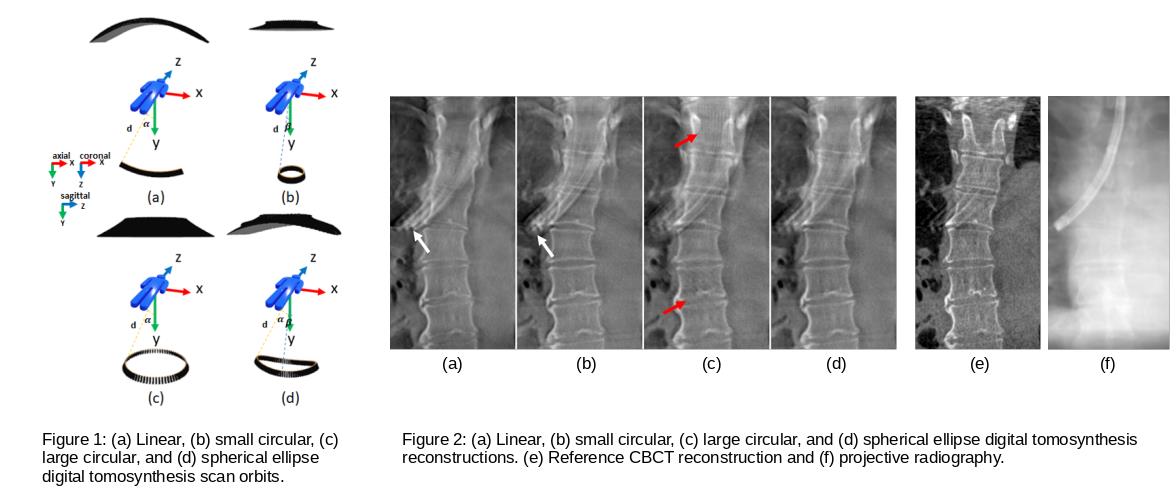

Finding and treating lung cancer at an early stage increases the chances of successful treatments and subsequently increases the survival rates. In this context, transbronchial needle biopsy procedures play an essential role in determining whether a spotted lung nodule is benign or malignant. However, the diagnostic yield of such procedures is largely dependent on an accurate nodule location identification during the intervention to take the biopsy samples from the correct locations. Medical imaging guidance is critical during such procedures. To navigate to the nodule, usually physicians rely on pre-operative computed tomography and intra-operative projective chest fluoroscopy. However, lung nodule location identification is highly challenging with projective fluoroscopy mainly due to the superimposition of the different lung structures in a 2D image. While intra-operative cone-beam computed tomography may provide exact 3D information, the radiation dose, the space requirements, and the timing it poses, burden its use in real practice. Therefore, digital chest tomosynthesis rises as a potential alternative for guiding bronchoscopy interventions. During this procedure, the C-arm rotates around the patient over a very limited angular range and a limited set of projection images are acquired and reconstructed providing a quasi-3D image. To address the limited depth resolution of tomosynthesis images with the conventional uni-directional scan orbits, Fatima et al. recently proposed a novel C-arm-based spherical ellipse multi-directional tomosynthesis scan orbit. Compared to conventional multi-directional tomosynthesis scan orbits, the proposed trajectory provides a good compromise between image quality and space requirements in the operating room. Fatima recently presented her work at the Fully3D conference with very promising initial simulation results. We are looking forward to implementing the new trajectory on our C-arm system and validating the results with real experiments.